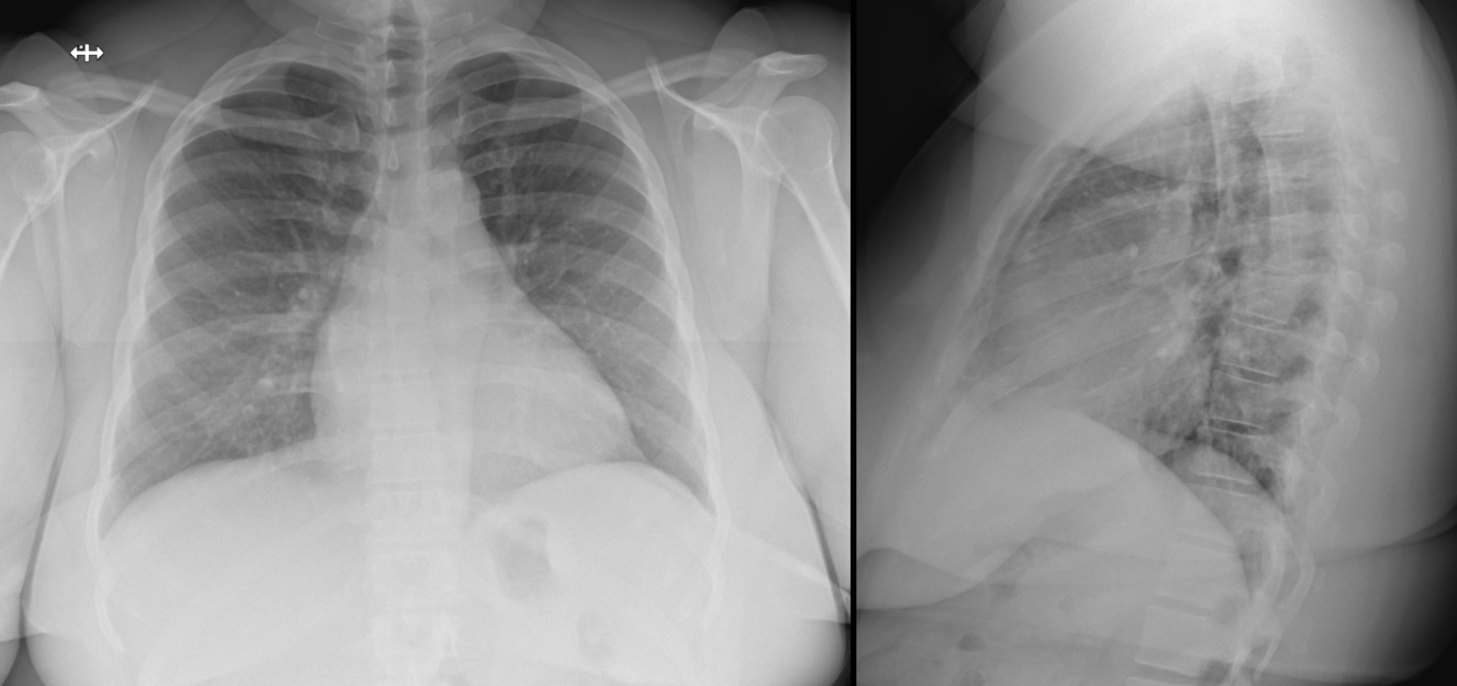

Name the cardiac abnormality.

What is left atrial enlargement?